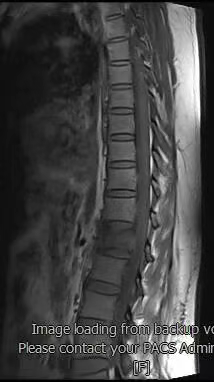

患者术前磁共振检查影像学表现:

患者术前的磁共振检查结果提示:L1椎体病变,结合病史考虑为转移癌。影像学评估提示L1椎体高信号表现,椎体高度未发生塌陷表现,椎管内容物无受压表现。患者临床腰椎功能活动受限,疼痛明显,相关生命体征平稳。